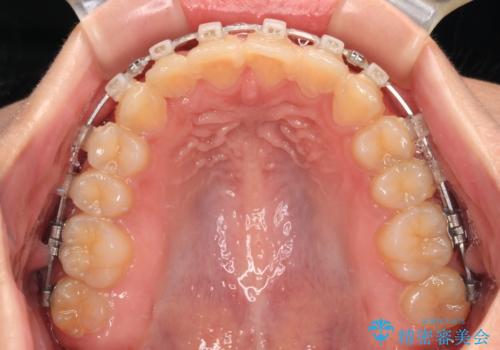

捻れて前に出ている前歯 ワイヤー装置での非抜歯矯正

- 捻れて前に出ている上顎前歯と全体的なデコボコを気にして来院された患者様です。

口元の突出感は強くなかったため非抜歯矯正での対応となりますが、捻転を改善する際に上顎前歯が前突する可能性があったため、上顎臼歯部にアンカースクリューを使用して、歯列が前方に転位しないようにすることとしました。

ワイヤー矯正でもインビザラインでも対応可能でしたが、上顎歯列が前方位であるときには、ワイヤー矯正の方がより良い仕上がりとなる可能性が高いため、ワイヤー矯正をおすすめいたしました。